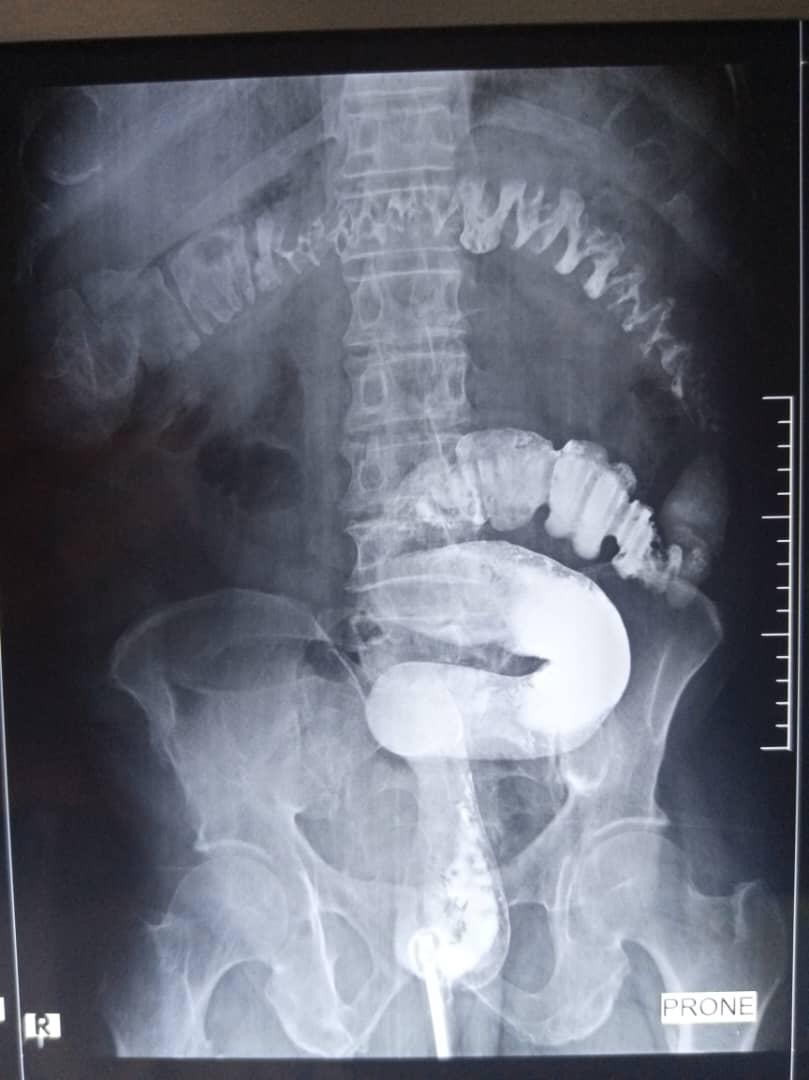

Intravenous Urography